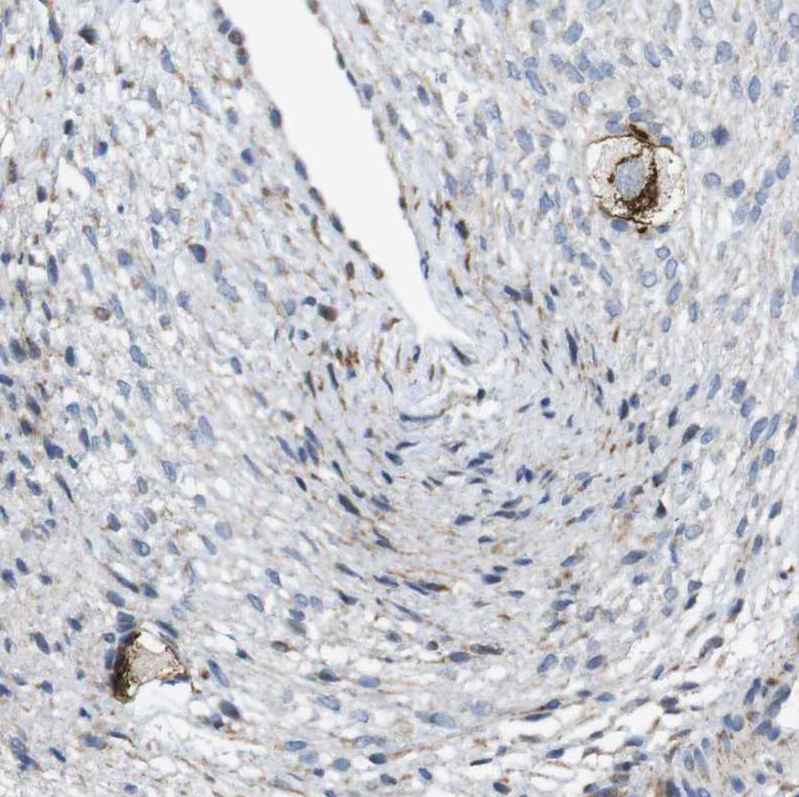

Immunohistochemical staining of human ovary shows moderate cytoplasmic/ membranous positivity in oocytes.